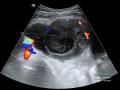

Diagnóstico por imagem em ginecologia - Quinto ano medicina